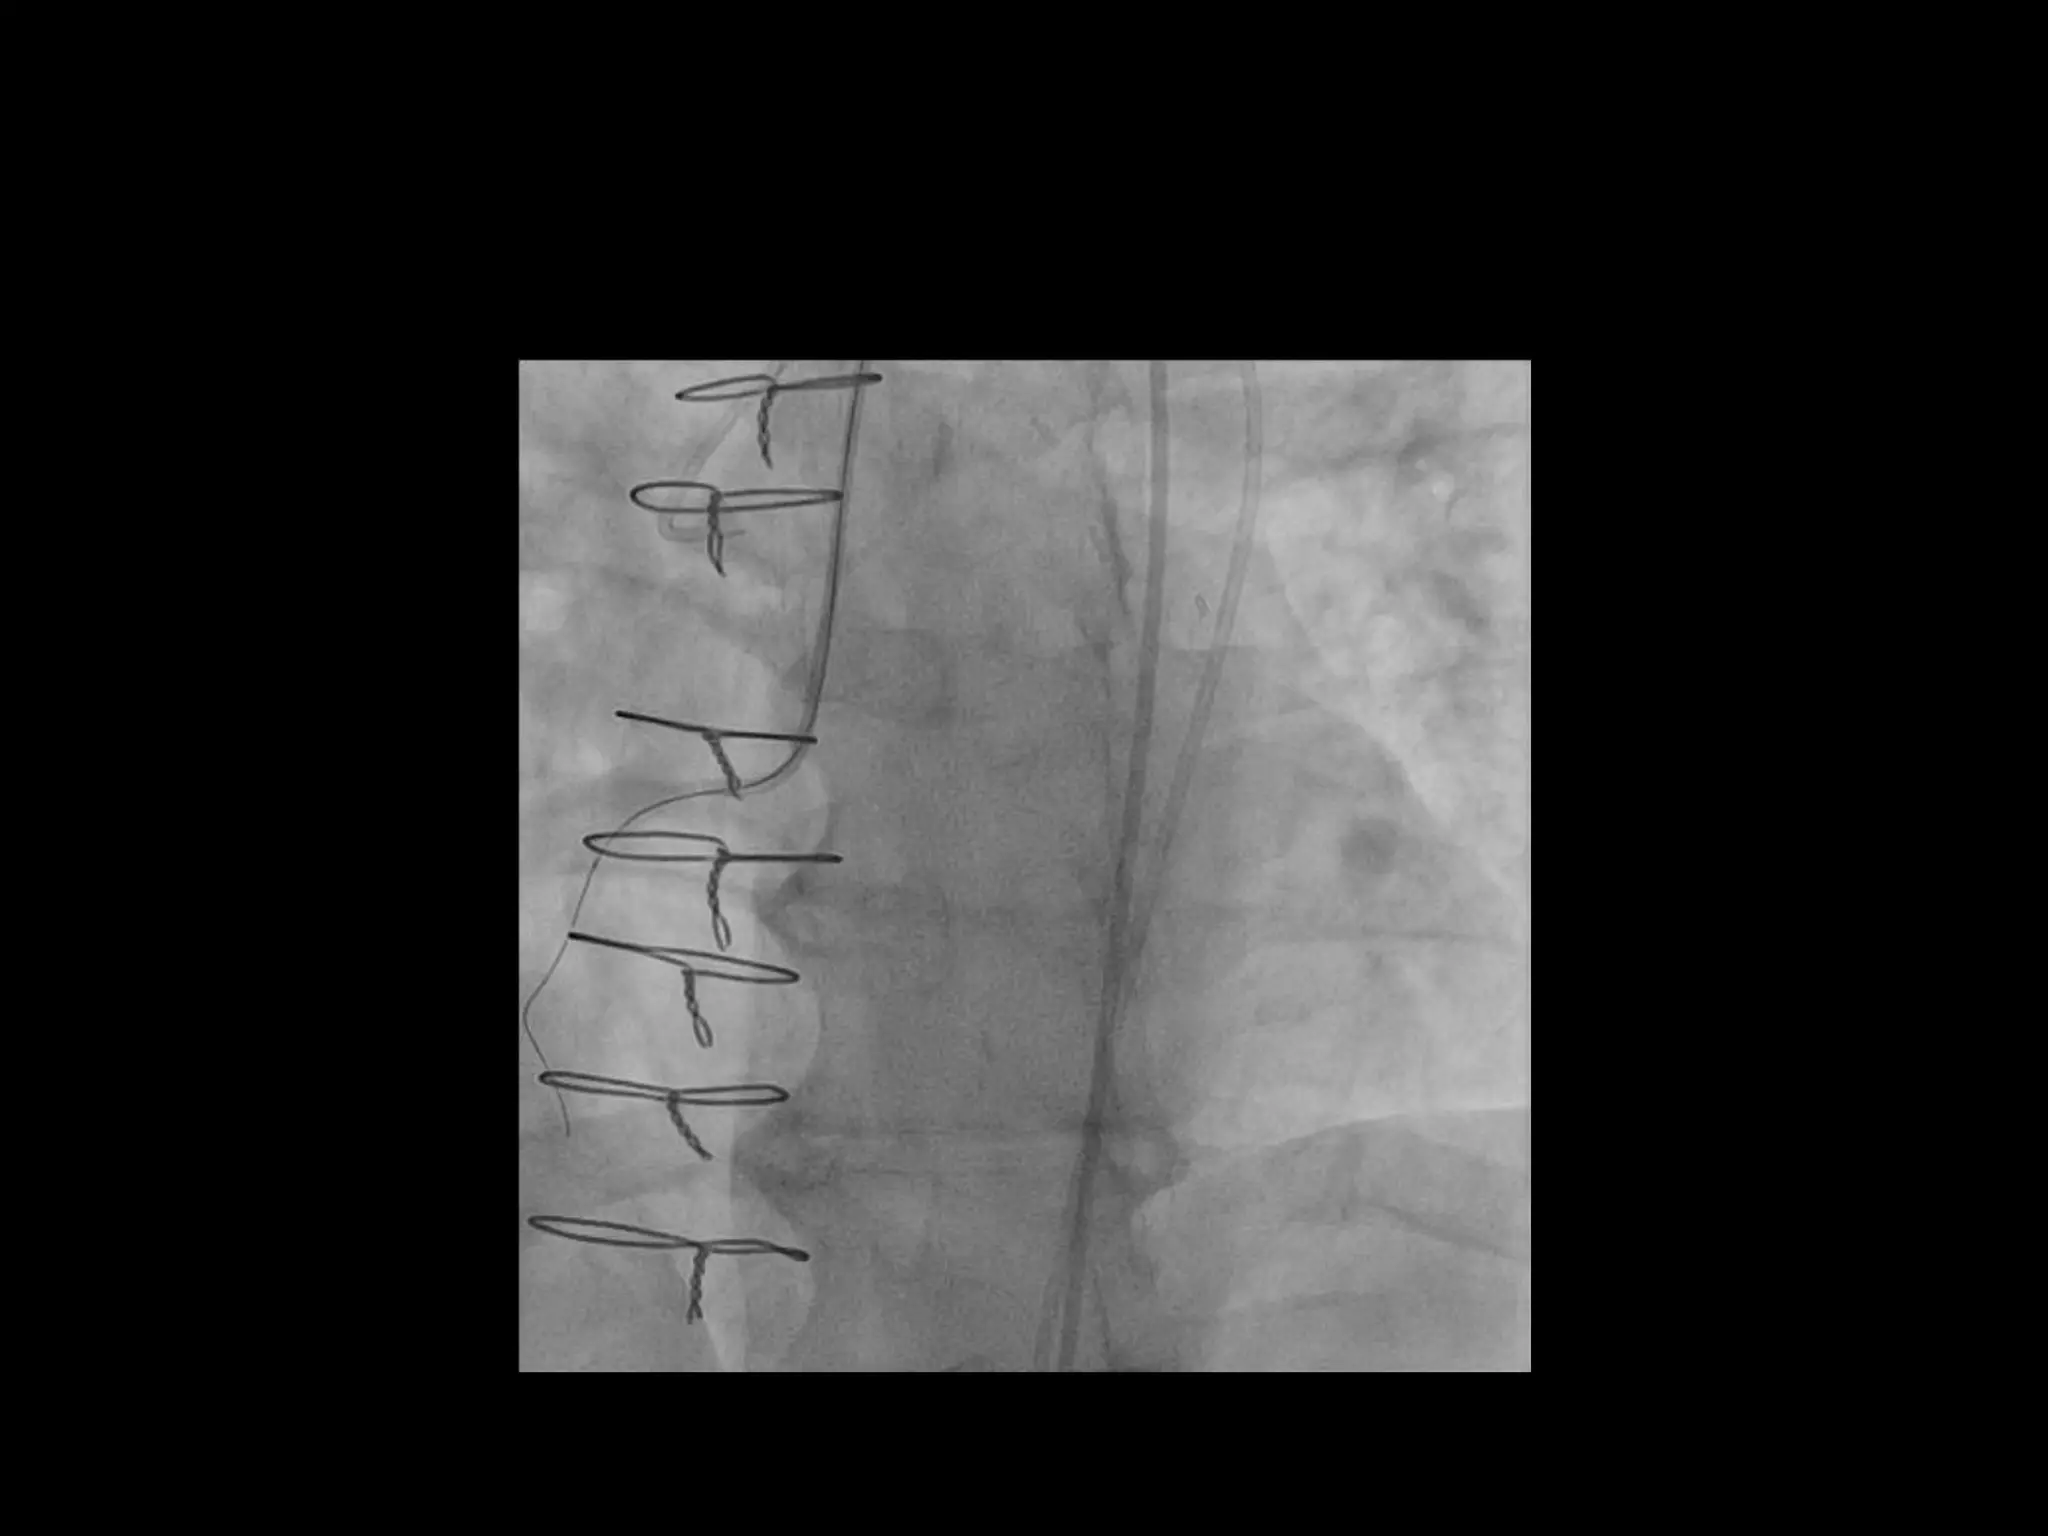

This document provides guidance on evaluating the feasibility of percutaneous coronary intervention (PCI) for a chronic total occlusion (CTO). Key factors to consider include: the patient's tolerance for a long procedure, contrast load, and radiation exposure; the CTO's proximal cap ambiguity, length, distal landing zone, and presence of interventional collaterals; and ensuring good quality angiography. With adequate planning and use of appropriate CTO techniques, feasibility is nearly always present for symptomatic patients. Success rates of CTO-PCI are reported to be 94% when using a planned approach.